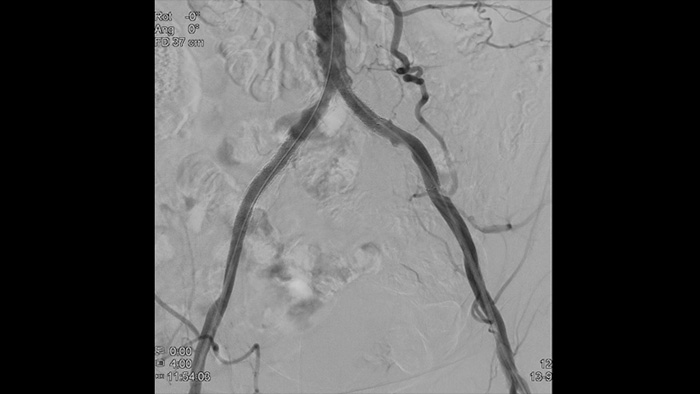

High-definition images of vessels with superior vascular detail to support precise treatment strategies, navigation and follow-up.